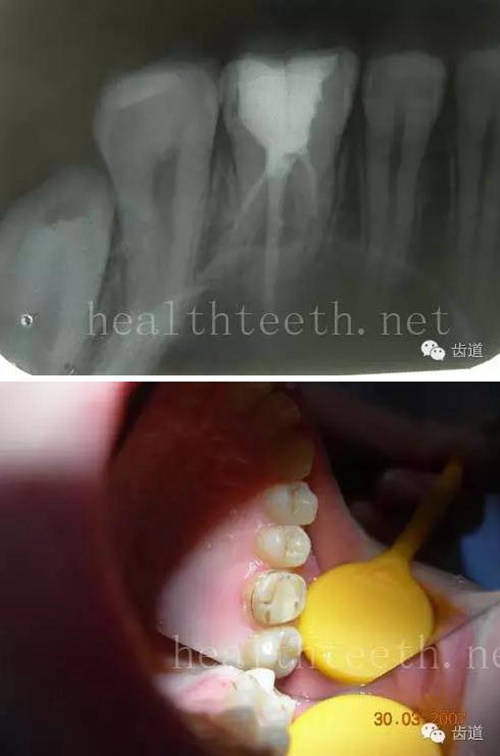

八、牙髓炎、根尖周炎

下面圖片都是慢性根尖周炎的病例,有了齲齒,進(jìn)一步發(fā)展就是牙髓炎,如果此時(shí)沒有得到及時(shí)的治療,疾病會逐漸發(fā)展破壞到根尖的骨質(zhì),將骨質(zhì)破壞后就在牙齦上出現(xiàn)一個(gè)膿瘺,此時(shí)患者不再感覺到牙齒的疼痛了,往往忽視了治療,但是這種不痛并不是疾病好轉(zhuǎn)了,而是因?yàn)榧膊〉难仔詽B出得到了引流,這個(gè)膿瘺會出現(xiàn)有時(shí)候變大了,有時(shí)候又變小了,但是如果不治療是不會自己愈合的,只有經(jīng)過完善的根管治療后才有好轉(zhuǎn)的可能,但是在疾病的治療中時(shí)間是起決定作用的,時(shí)間拖得越晚,好轉(zhuǎn)的可能性越小,經(jīng)過根管治療后如果膿瘺還是沒有消失,就需要做根尖刮治術(shù),如果仍然沒有好轉(zhuǎn),就只能做根尖切除術(shù)了,這對牙齒的穩(wěn)固是不利的。下面圖片中在膿瘺中插入了一個(gè)牙膠尖,是我們做根管充填用的材料,是非常軟的,就是在口腔牙齦瘺管的地方插進(jìn)去,通過拍牙片可以清晰地看到它到達(dá)的位置,從而確定發(fā)病的牙齒,此處是為了讓大家看得更清楚。

門牙兩個(gè)膿瘺

69.jpg

烤瓷牙修復(fù)后牙齦出現(xiàn)兩個(gè)膿瘺,插入牙膠尖,牙片顯示牙膠尖到達(dá)的位置就是根尖炎癥的位置,根尖骨質(zhì)密度降低(發(fā)黑的地方)

牙齒根尖膿瘺,治療前、中、后的圖片對照,完善根管治療后膿瘺明顯消失了